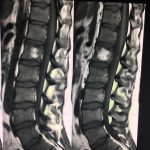

- α

- β

- γ

- δ

- ε

- στ

Εικόνα 2 α,β: Μαγνητική τομογραφία της Ο,Μ,Σ,Σ, (200) Μετωπιαία λήψη (coronal) γ,δ, οβελιαία λήψη (saggital) ε,στ, εγκάρσια λήψη (axial) ακολουθίες Τ1 και Τ2 . Οι λήψεις αυτές αναδεικνύουν την ύπαρξη ευμεγέθους αιμαγγειώματος εντός του σώματος του 1ου οσφυϊκού σπονδύλου.